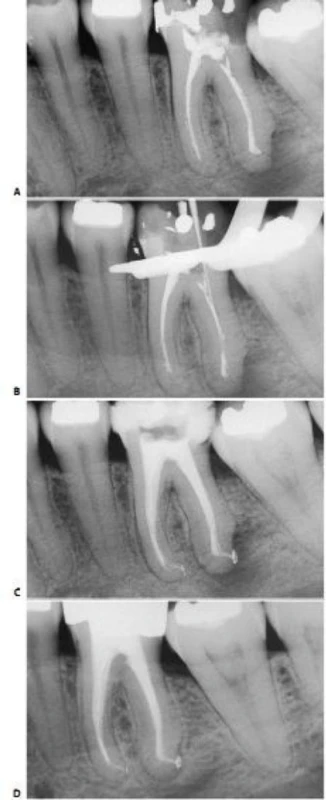

* Một ống tủy ở trong một chân xa, trong khi ở chân gần có hai ống tủy riêng biệt (hình 11.121) hoặc hai ống tủy gặp nhau tại một lỗ chóp (hình 11.122).

Hình 11.121. Răng cối lớn thứ hai hàm dưới với một ống tủy xa và hai ống tủy gần. A. Phim trước điều trị. B. Phim sau điều trị hai năm.

Hình 11.122. Một răng cối lớn thứ hai hàm dưới với một ống tủy xa và hai ống tủy gần giao nhau tại cùng một lỗ chóp. A. Phim trước điều trị. B. Phim sau điều trị.

* Những trường hợp khác, chân gần có thể có một ống tủy ở chính giữa, vì vậy răng có một ống tủy ở phía xa và một ống tủy ở phía gần (hình 11.123). Để chắc chắn rằng chân gần có một ống tủy đơn, cần phải kiểm tra vị trí miệng ống tủy ở sàn buồng tủy và chụp X-quang theo nhiều hướng khác nhau. Đôi lúc có thể tìm thấy dấu hiệu thủng sàn ở phía trong xoang tủy do nha sĩ trước đã cố gắng tìm ống tủy gần trong trong khi chân gần chỉ có một ống tủy.

Hình 11.123. Răng cối lớn thứ hai hàm dưới với một ống tủy ở chân xa và một ống tủy ở chân gần. A. Xoang tủy: Hai ống tủy tại đáy của rãnh nằm giữa sàn tủy. Bên phải có dấu của mũi khoan (hướng về mặt lưỡi). Nha sĩ trước đó đã cố tìm ống tủy gần trong vốn không tồn tại. B. Phim sau điều trị: hai ống tủy nằm ở hai chân răng riêng biệt, thông nhau rõ ràng ở vị trí lỗ chóp của hai chân.